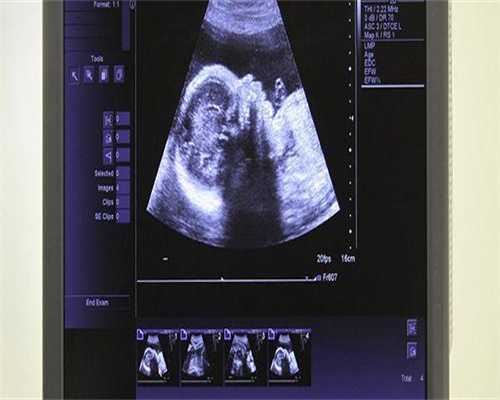

第三、B超监测:通过B超检测卵泡的逐渐长大、排出,非常准确,是监测卵泡有无排卵的金标准。一般对月经规律,其周期30天左右的女性,一个周期做3次左右,即月经周期的第10-12天做第一次B超,根据卵泡发育的大小,3天左右进行下次监测,如卵泡长大可指导同房,同房后再去医院监测,明确有无排卵。